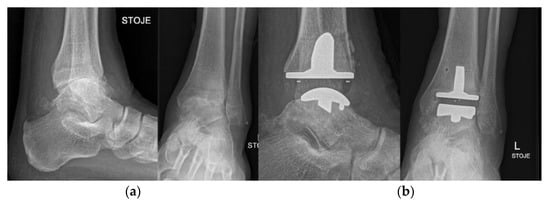

5.7. Ankle and Foot